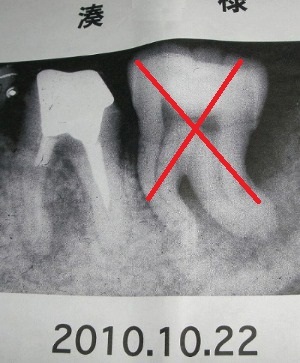

歯周病での奥歯7番は抜歯との診断。何とか治療できないでしょうか?

前歯の中でも、犬歯(八重歯)はトラブルが起きやすい歯です。 海外に滞在しており5月まで帰国しない予定のところ、歯茎が腫れ膿んでしまったので歯医者に行ったのですが、歯医者の医師に抜歯した方がいい今抜歯しないと菌が発生したり骨に影響がある…ということで抜歯を進められ抜歯をしました。 発熱、腫れ、痛みはどのくらい続きますか? カテゴリ 抜歯 相談者 pen様 年齢 53歳 性別 女性 質問事項が3つあります。 痛み・腫れについて 1. その中でも 代表的なのは以下の症状。 当時は「どうしても残してほしい」と先生にお願いして何とか治療してもらいました。 この増井の効果時間を過ぎてからが問題。